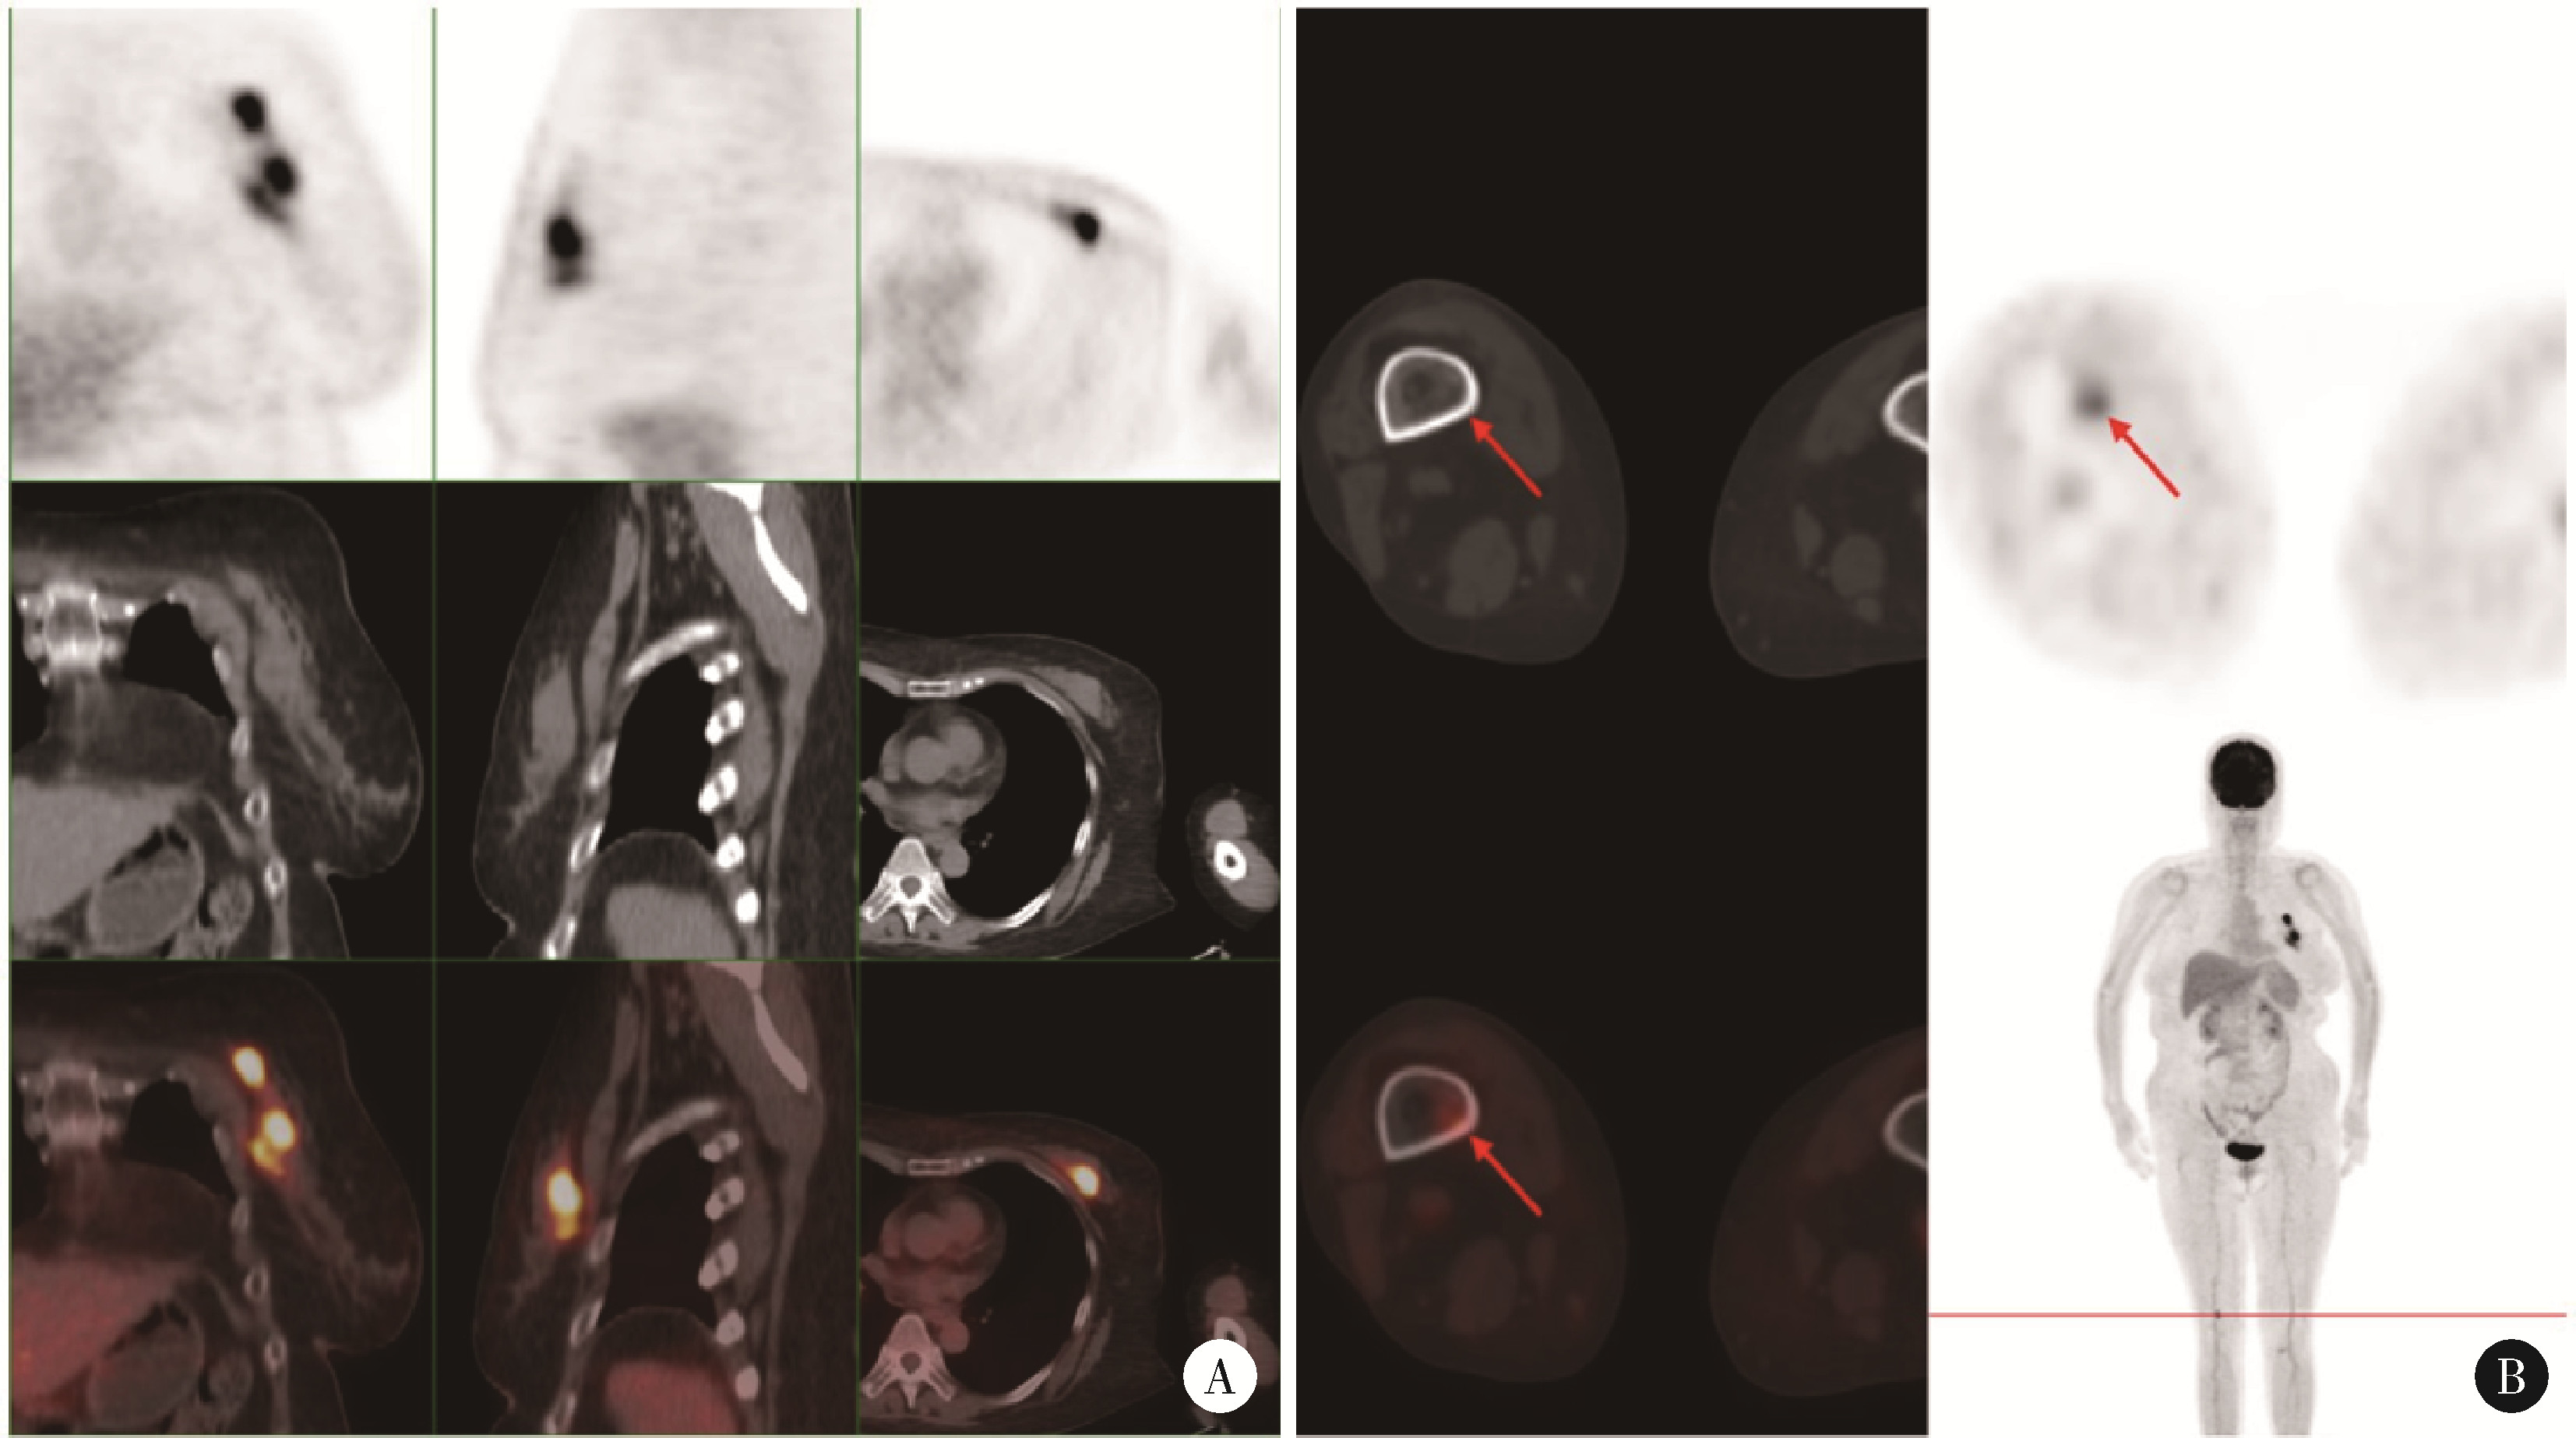

Figure 1

PET/CT images of the patient (October 2023) A, left breast, multiple foci of increased flurodeoxyglucose (FDG) metabolism with a maximum standardized uptake value (SUVmax) of 10.1; B, right femur (distal), increased FDG metabolism with an SUVmax of 4.6."